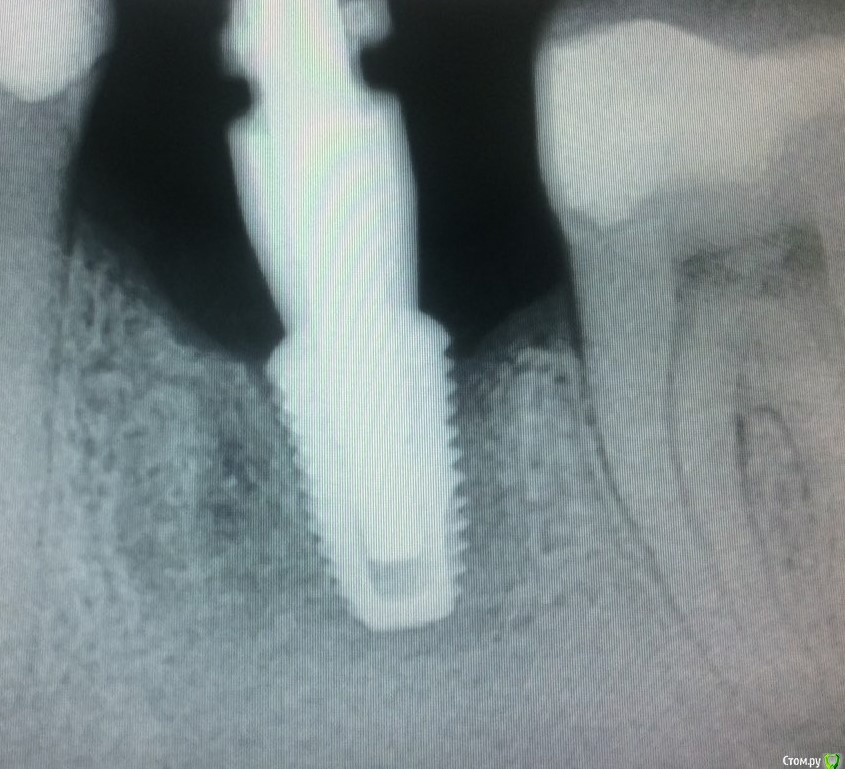

Женька Опубликовано 20 января, 2021 Автор Поделиться Опубликовано 20 января, 2021 Все хорошо закончилось?Вот в субботу и узнаю.Сегодня был осмотр, выкручивать, по совету коллег я всё-таки не стал. Последовал совету Уразбахтина И. Сделал прицелы (завтра скину с работы). Криминала какого-то я не отметил, даже положительная динамика вроде прослеживается... Если бы не жалобы пациентки и страшная кт, вообще бы не обратил внимание... Как считаете, какой торк на выкручивание считать приемлемым? Ссылка на комментарий

Женька Опубликовано 21 января, 2021 Автор Поделиться Опубликовано 21 января, 2021 Все должно хорошо закончится, вы переживаете, не безразлично, это хорошо. Я против слишком больших торков, особенно в плотной кости и узком гребне. Ха! Самую страшную КТ показал Колесников, типа " дед" кошмарит новичка))))Снимки подписаны датами. Есть же какая то динамика, что думаете? И всё-же, какое усилие на выкручивание считать приемлемым? Я же правильно понимаю, что 45 это про первичную стабильность. А для вторичной это пшик? Ссылка на комментарий

red_butler Опубликовано 21 января, 2021 Поделиться Опубликовано 21 января, 2021 на снимках все нормально, торк для проверки должен быть как минимум равен торку при фиксации винта абатмента, у дентиума это 30 или 35Н/см 2 Ссылка на комментарий

Irouil Опубликовано 21 января, 2021 Поделиться Опубликовано 21 января, 2021 (изменено) 35 давайте, если винт не интегрирован - никакой "вторичной" нет, так что там до 35 не дойдёт, если интегрирован - ему действительно пшик Снимки огонь, но я ставлю на то, что медиальный выкрутите( Изменено 21 января, 2021 пользователем Irouil Ссылка на комментарий

Raystom Опубликовано 21 января, 2021 Поделиться Опубликовано 21 января, 2021 (изменено) Меня тоже такие мысли посещают... но прошло почти 3 месяца, ставили в начале ноября, сыграют ли лишние 2 недели?Торк был 45. Через 8-12 недель уже можно начинать работать с имплантатом. На мой взгляд дольше этого срока в данном случае выжидать смысла не вижу. Если всё пошло по пути фиброинтеграции, то она уже есть. Если нет, то к этому времени уже должна быть грубоволокнистая кость и вторичная стабильность Изменено 21 января, 2021 пользователем Raystom Ссылка на комментарий

Женька Опубликовано 6 февраля, 2021 Автор Поделиться Опубликовано 6 февраля, 2021 (изменено) 35 давайте, если винт не интегрирован - никакой "вторичной" нет, так что там до 35 не дойдёт, если интегрирован - ему действительно пшик Снимки огонь, но я ставлю на то, что медиальный выкрутите(Ставка не сыграла) почти 50 на вкручивание и выкручивание попробовал. ДержитИ неумелый забор с бугра, потом нормальный сдт с нёба и кривая подсадка в области винтов...правильно Колесников в соседней теме говорил про отсутствие знаний Изменено 6 февраля, 2021 пользователем Женька Ссылка на комментарий